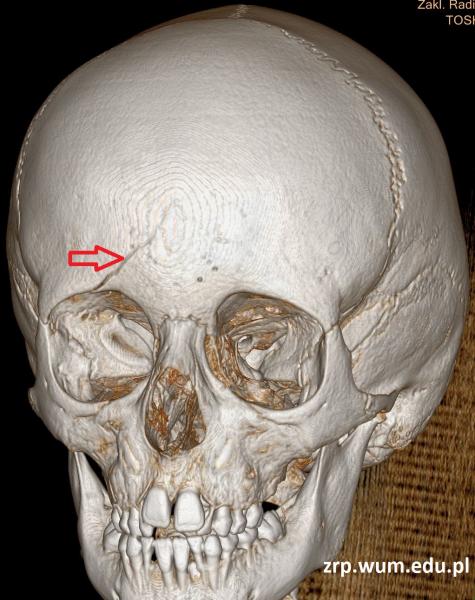

Przypadek 58: 6-latek po urazie głowy okolicy czołowej - zderzenie z kolegą.

Rozpoznanie: w wykonanym badaniu TK głowy - złamanie kości czołowej po stronie prawej. Szczelina złamania obejmuje łuskę kości czołowej (strzałka) oraz górną ścianę oczodołu prawego (nie pokazano na zdjęciach). Bez zmian pourazowych śródczaszkowo.